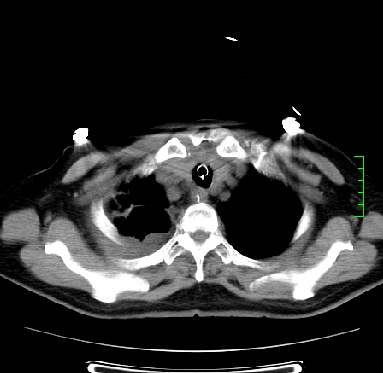

icu病人,几天都没明确诊断。m,76y,咳嗽、咳痰1周,伴气促,右胸痛入院,pe:t38.3c p135 r25 bp135/85。双肺可闻及大量湿罗音,心、腹未见明显异常。诊断:1心衰?2肺部感染?3冠心病?

11号ct